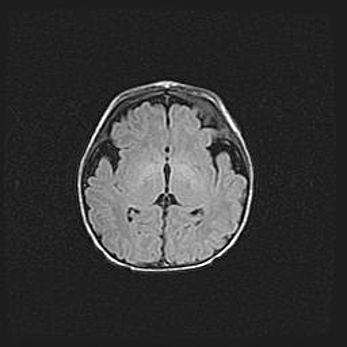

Сообщающаяся гидроцефалия. Кистозная энцефаломаляция головного мозга.

Возраст: 3 месяца 4 дня

Вес: 3100 г

Пол: женский

Окружность головы: 34 см

Срок гестации: 31 неделя

Кистозная энцефаломаляция головного мозга - одна из форм поражения головного мозга в детском возрасте. Характеризуется возникновением множественных и распространённых кист в коре, белом веществе и подкорковых образованиях головного мозга у плодов, новорождённых и детей раннего возраста. Развитие кистозной энцефаломаляции связано с внутриутробной асфиксией и гипотонией, родовой травмой, тромбозом синусов, пороками развития сосудов, инфекциями, сепсисом и другими причинами. Наиболее значимые инфекционные агенты: вирусы простого герпеса, цитомегалии, краснухи, токсоплазмы, энтеробактерии, золотистый стафилококк и другие.